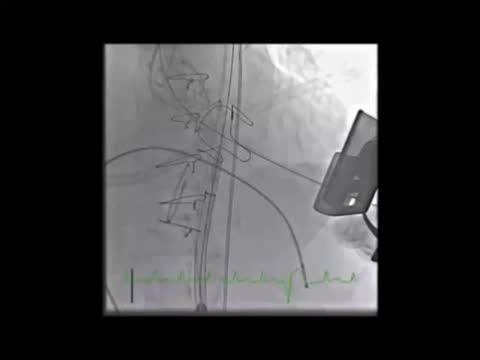

The initial plan was to implant a 23-mm CoreValve Evolut R (Medtronic, Irvine, CA) in aortic position (transfemoral approach) and a 29-mm Edwards SAPIEN 3 in mitral position (transapical approach). The procedure began with a successful left transfemoral approach with a 14-F Fast-Cath sheath, and the left coronary artery was protected with an angioplasty guidewire. Due to extreme difficulty in retrograde crossing of the aorta, a transapical-transfemoral loop approach was considered. The loop was created after gaining transapical access (Figure 2A), through which an INFINITI MPA 2 catheter (5.0 Fr×125 cm, Cordis) was used to advance an Emerald J wire (0.035″×260 cm) anterogradely until it reached the left common iliac artery, where it was captured with a 25-mm Amplatz Goose Neck snare (Figure 2B). After wire externalization at the left groin, the MPA 2 catheter was removed from the apical access and inserted via the groin, enabling the Emerald J wire to be exchanged for an Amplatz Extra Stiff guidewire (0.035″×260 cm) via a left transfemoral route (Video 2). The CoreValve was then successfully advanced into the aortic root and implanted in a suprannular aortic position under rapid pacing (Figure 2C and Video 3), 7 mm below the radiopaque Mitroflow ring. The left coronary ostium was unobstructed. Subsequently, the mitral valve-in-valve Edwards was successfully implanted transapically, without complications (Figure 2D and Video 4). Intraprocedural transesophageal echocardiography showed normal gradients (mean aortic gradient 11 mmHg, mean mitral gradient 3 mmHg) (Figure 2E and F) and a mild aortic perivalvular leak (Video 5). There were no immediate procedural complications. Due to contrast nephropathy and development of anuria (serum creatinine increased to 5.1 g/dl), the patient needed temporary renal replacement therapy, which was discontinued after two and a half weeks due to resumed diuresis. Before discharge, TTE revealed a small paravalvular aortic leak and normally functioning prosthetic valves. The patient was discharged in New York Heart Association (NYHA) functional class II on the 67th day with mild anemia (hemoglobin 11.5 g/dl), creatinine 1.0 mg/dl and eGFR 30 ml/min/1.73 m2.

(A) A long Emerald J wire passes through the stenotic Mitroflow, in which it is captured with an Amplatz Goose Neck snare (B); valve-in-valve implantation of a 23-mm CoreValve Evolut R in aortic position by the transfemoral route (C); implantation of a 29-mm Edwards SAPIEN 3 in mitral position by the transapical route (D); new aortic (E) and mitral (F) bioprosthetic valves visualized by transesophageal echocardiography during the procedure following implantation.